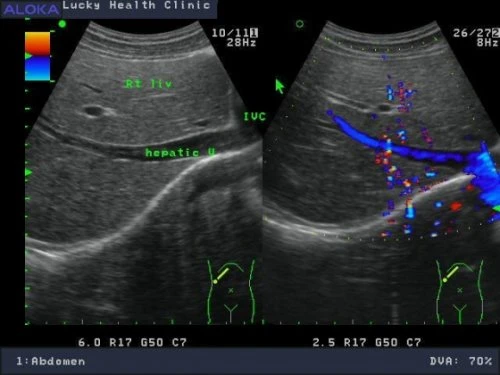

正常肝臟![]() Rt liv :右葉肝臟 IVC :下腔靜脈 hepatic V :肝靜脈 ![]() Lt liv :左葉肝臟 , LHV :左側肝靜脈 , LPV :左側肝門靜脈 , IVC :下腔靜脈 , SMA :上腸繫膜動脈 , SV :脾靜脈 , P :胰臟 , AORTA:主動脈 肝癌 ![]() 肝硬化合併早期肝癌1.4公分 ![]() 轉移性肝癌 ![]() 肝癌局部復發 1.6 公分 ![]()